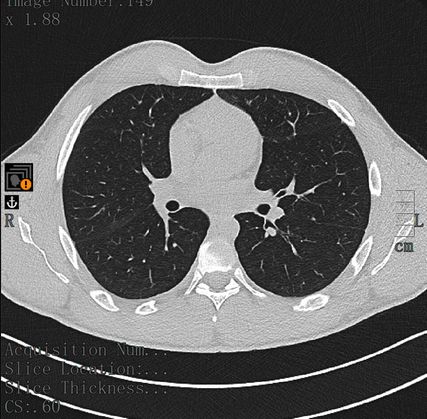

Mittels Pulmonalisangiografie-CT konnte eine Lungenembolie ausgeschlossen werden, dafür zeigten sich diffuse und ubiquitär verteilte alveoläre Konsolidierungen (Abb. 1). Eine ältere Bildgebung zum Vergleich lag nicht vor. In Anbetracht der bildmorphologischen Veränderungen wurde unter anderem die Verdachtsdiagnose einer Vaskulitis gestellt.